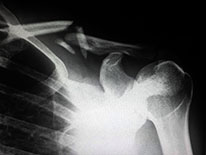

Radiologists Question Shielding Patients